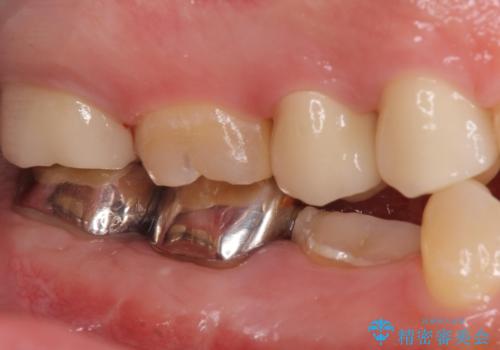

- 口の中を予算の範囲内でできるだけきれいにしたいとのことで来院された患者様です。

矯正治療と虫歯治療を組み合わせてご提案しましたが、ご予算との兼ね合いで虫歯治療のみを行うこととなりました。

奥歯は十分な歯の高さがなかったため、クラウンをかぶせる前に歯周外科治療で歯の高さを出しています。